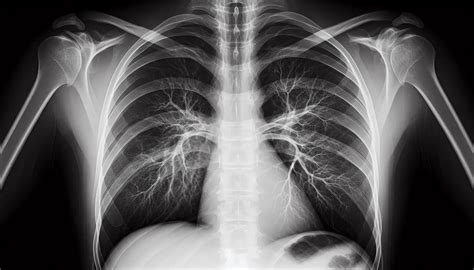

Para poder asegurarnos de que el paciente sufre de caries interproximales, el odontólogo le realizará una radiografía oral y una exploración dental. La prueba diagnóstica más adecuada para las caries interproximales será una radiografía oral y una exhaustiva exploración dental. Las visitas periódicas a nuestro dentista para revisión y una adecuada rutina diaria de higiene bucal son la mejor forma de mantener este problema bajo control.

Tipos de Radiografías Dentales

Igual que los médicos, los dentistas utilizan las técnicas radiológicas para estudiar con más detalle los casos que atienden en sus gabinetes. Existen varios tipos de radiografías dentales, que dan información diferente a cada paciente:

- Ortopantomografía: También llamada radiografía dental panorámica, es el tipo de radiografía dental más común. Muestra la totalidad de la estructura facial y mandibular (arcadas superior e inferior, huesos maxilares, mandíbula y estructuras de soporte). De hecho, lo más corriente es que se efectúe en la primera visita del paciente a la clínica, durante su revisión general. Con un aparato de rayos X, se toma una imagen completa de la boca del paciente. Gracias a las ortopantomografías, los dentistas pueden identificar patologías y anomalías en las raíces dentales o en dientes incluidos: que no han erupcionado de la encía. La ortopantomografía (radiografía de toda la boca) nos ayudará a determinar el nivel óseo general, presencia de terceros molares (muelas del juicio), lesiones en las raíces de los dientes (granulomas infecciosos), etc.

- TAC Dental: Muy similar a los escáneres que se acostumbran a usar en medicina, el TAC Dental toma cientos de imágenes desde diferentes ángulos de la boca del paciente. Estas radiografías son enviadas a un ordenador, que genera una imagen virtual en 3 dimensiones de la boca del paciente.

- Cefalometría o telerradiografía: Es un tipo de radiografía que, en el ámbito odontológico, prácticamente solo se usa en los estudios previos a una ortodoncia.

- Radiografía de aleta/mordida: En esta clase de radiografías dentales, la imagen se toma dentro de la boca del paciente. Se utilizan sobre todo para identificar casos de caries interproximales (entre los dientes del paciente) o problemas en las raíces de los dientes. Aunque no sea lo ideal, para facilitar su realización, a veces se le pide el paciente que sea él mismo el que sujete la placa radiológica. La placa se coloca a lo largo de la mordida del paciente, para obtener una imagen completa de las coronas dentales del paciente.

Cualquier tipo de radiografía no es útil para diagnosticar las caries. Las idóneas para la detección de caries son las radiografías periapicales o las de “aleta de mordida”. Son radiografías de pequeño tamaño y alta sensibilidad que nos muestran con gran detalle las coronas y raíces de los dientes.

La radiografía dental ayuda a diagnosticar enfermedades y lesiones que en una exploración clínica no son visibles. Las radiografías dentales nos pueden revelar:

- Infecciones (abscesos o quistes).

- Pérdida de hueso.

- Tumores.

- Anomalías del desarrollo.

- Caries dentales interproximales o en zonas no visibles.

- Fracturas.

- Cálculo subgingival.

¿Qué aspecto tiene una caries en una radiografía?

La desmineralización y destrucción de las capas del diente se observa como una imagen radiolúcida (zona negra alrededor/dentro del diente). En la consulta dental realizamos controles radiográficos periódicos. Se hacen cada 6, 9 o 12 meses, dependiendo del riesgo de caries del paciente, la presencia de múltiples reconstrucciones interproximales (interdentales), etc.

En la imagen de la izquierda se aprecia una caries debajo de un empaste antiguo.

Es importante tener en cuenta que el diagnóstico temprano de las caries repercutirá en un mejor pronóstico del diente. En obturaciones antiguas (empastes/reconstrucciones) controlaremos que los márgenes de las restauraciones estén correctos, ya que en el material artificial no se producirán caries, pero en el tejido dental de alrededor sí podrían aparecer filtraciones. En la imagen que señala la flecha vemos una imagen radiolúcida (oscura) que indica la falta de material dental, la presencia de una zona “hueca”. Caries.

Conclusiones del estudio

La utilización de técnicas radiográficas, ya sean convencionales o digitales, incrementa el número de caries diagnosticadas frente a la exploración clínica convencional. Se diagnosticaron 3.23 veces más lesiones de caries con la radiología digital y 2.88 con la radiografía convencional que con la exploración visual. El 94% de estas nuevas caries eran de localización interproximal.